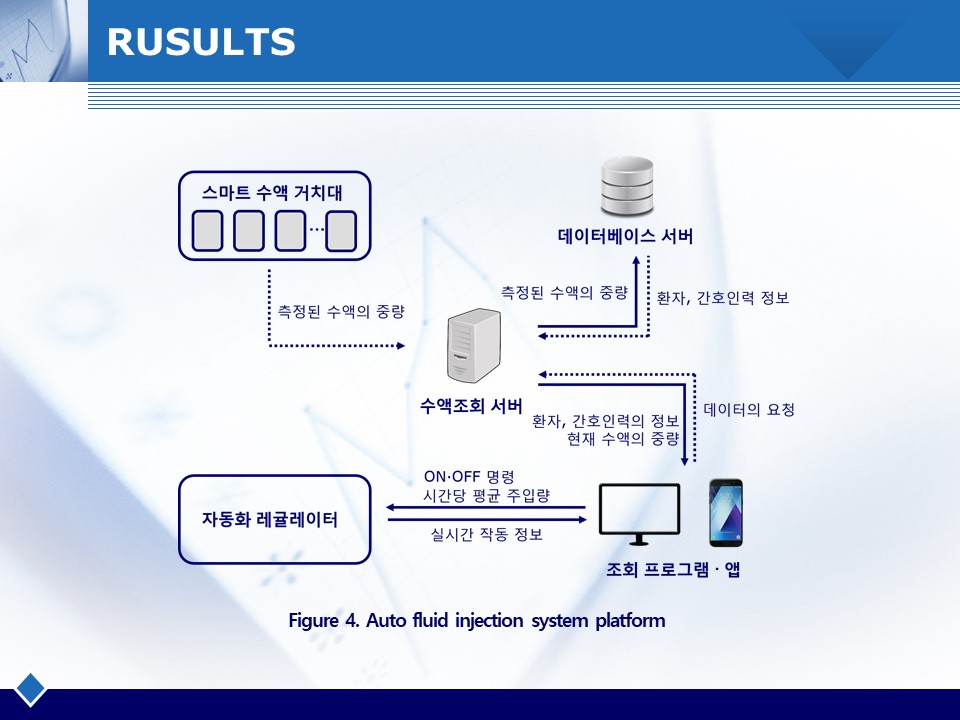

수액투여 시 의료사고를 방지하고 정확한 양의 수액을 투여하기 위한 자동화 및 모니터링 시스템을 개발함. 스마트 수액 거치대를 통해 실시간 수액의 중량변화를 모니터링하고, 오토-레귤레이터가 자동으로 유량을 조절함. 수액 거치대와 오토-레귤레이터를 설계 및 제작하고 주입오차 테스트를 통해 정밀도를 측정함.